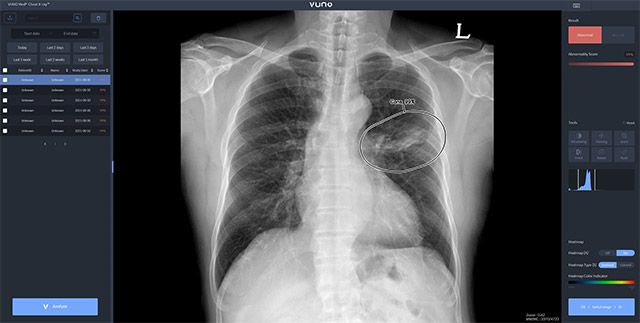

자이드 군 병원에 도입된 솔루션은 이동형 엑스레이 장비에 뷰노의 AI 기반 흉부 엑스레이 판독 보조 솔루션 뷰노메드 체스트 엑스레이™(VUNO Med®-Chest X-ray™)를 탑재한 패키지 제품이다.

별도의 차폐 시설 없이 다양한 상황에서도 쉽게 환자의 흉부 엑스레이 촬영을 할 수 있는 이동형 장비에 인공지능을 연동해 수 초 이내에 판독 결과를 확인할 수 있어 의료 인프라가 낙후한 지역에서도 진단 편차를 줄이고, 판독 효율성과 정확도를 크게 높일 수 있다.